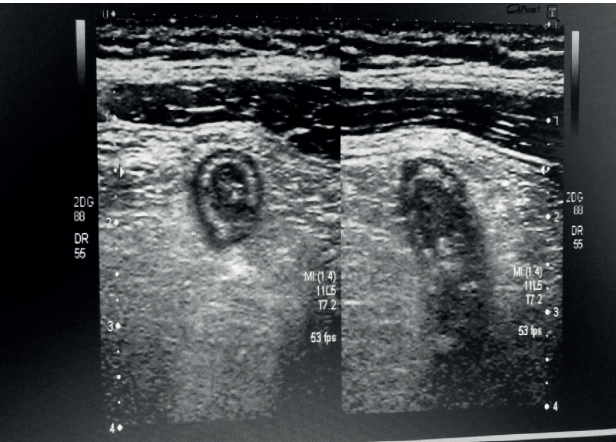

Com base na imagem acima, assinale a alternativa que apresenta achado ultrassonográfico compatível com apendicite aguda.